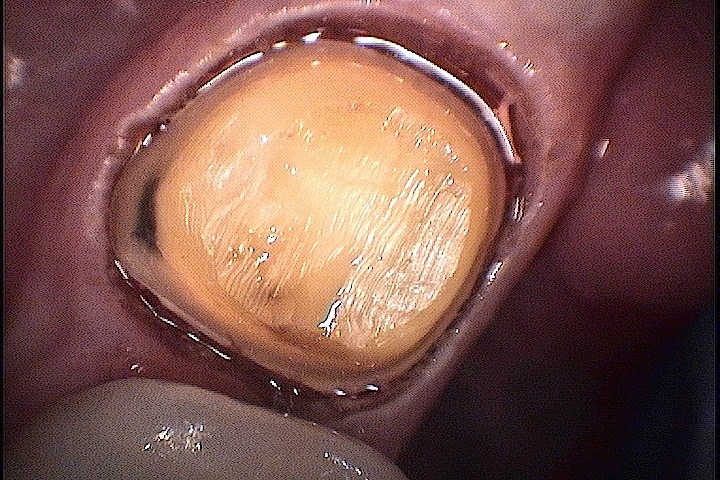

Modified preparation – Book picture Perfect impression made

Perfect impression made Thanks to Accutech Dental Lab – Mr. Thomas – my right hand

Thanks to Accutech Dental Lab – Mr. Thomas – my right hand Beautiful Crown, Perfect fit and precise margins. This is what is done at my office

Beautiful Crown, Perfect fit and precise margins. This is what is done at my office Perfect Margins

Perfect Margins